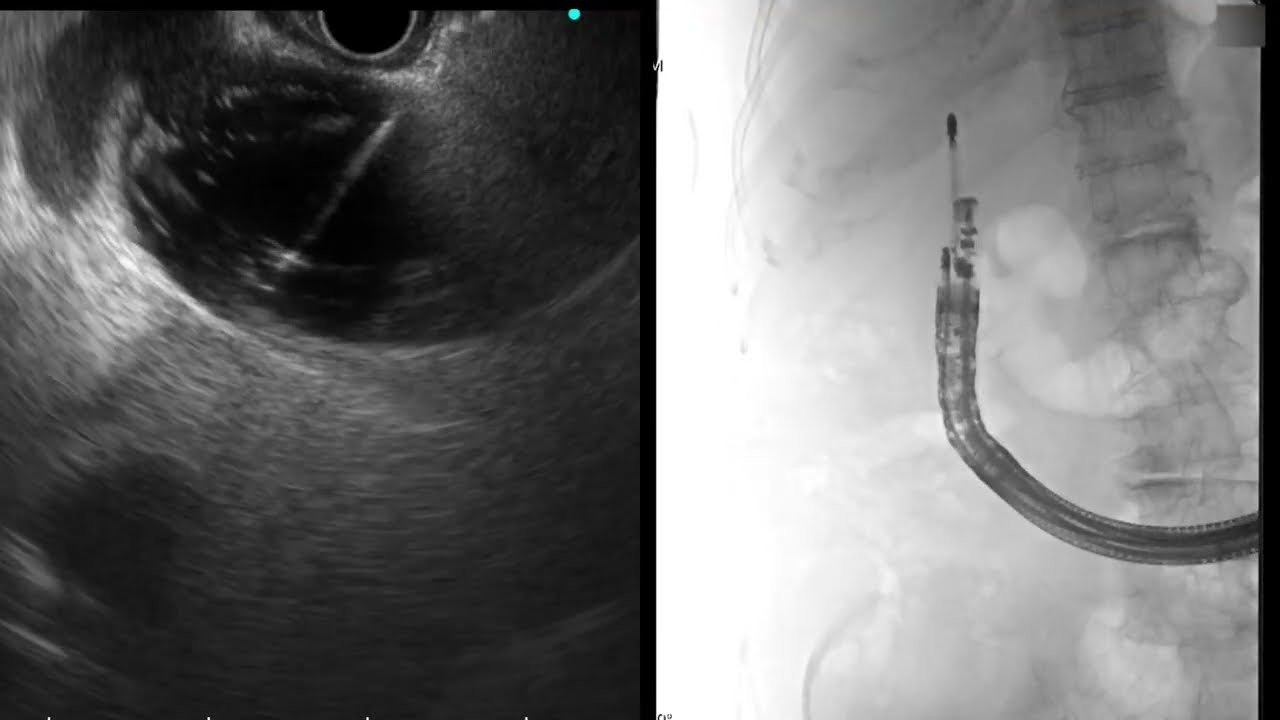

EUS-guided EGBD case with Z-EUS IT. Case video by prof. Anthony Y.B. Teoh (HK) HANAROSTENT® HOT Plumber™ with Z-EUS IT ™ Lumen Apposing Metal Stent (LAMS, Hot LAMS)